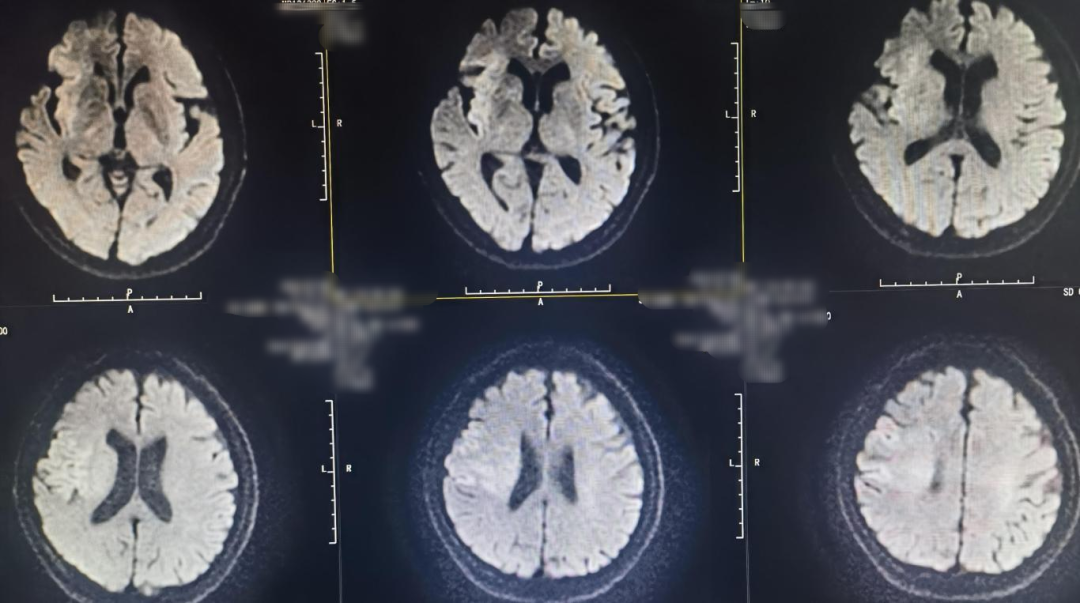

Preoperative MRI:

10-day postoperative follow-up cranial CT showed infarction in the right cerebral hemisphere.

Physical examination: patient alert and responsive, speech less fluent, left limb muscle strength grade 3, right limb strength normal. NIHSS score: 6.